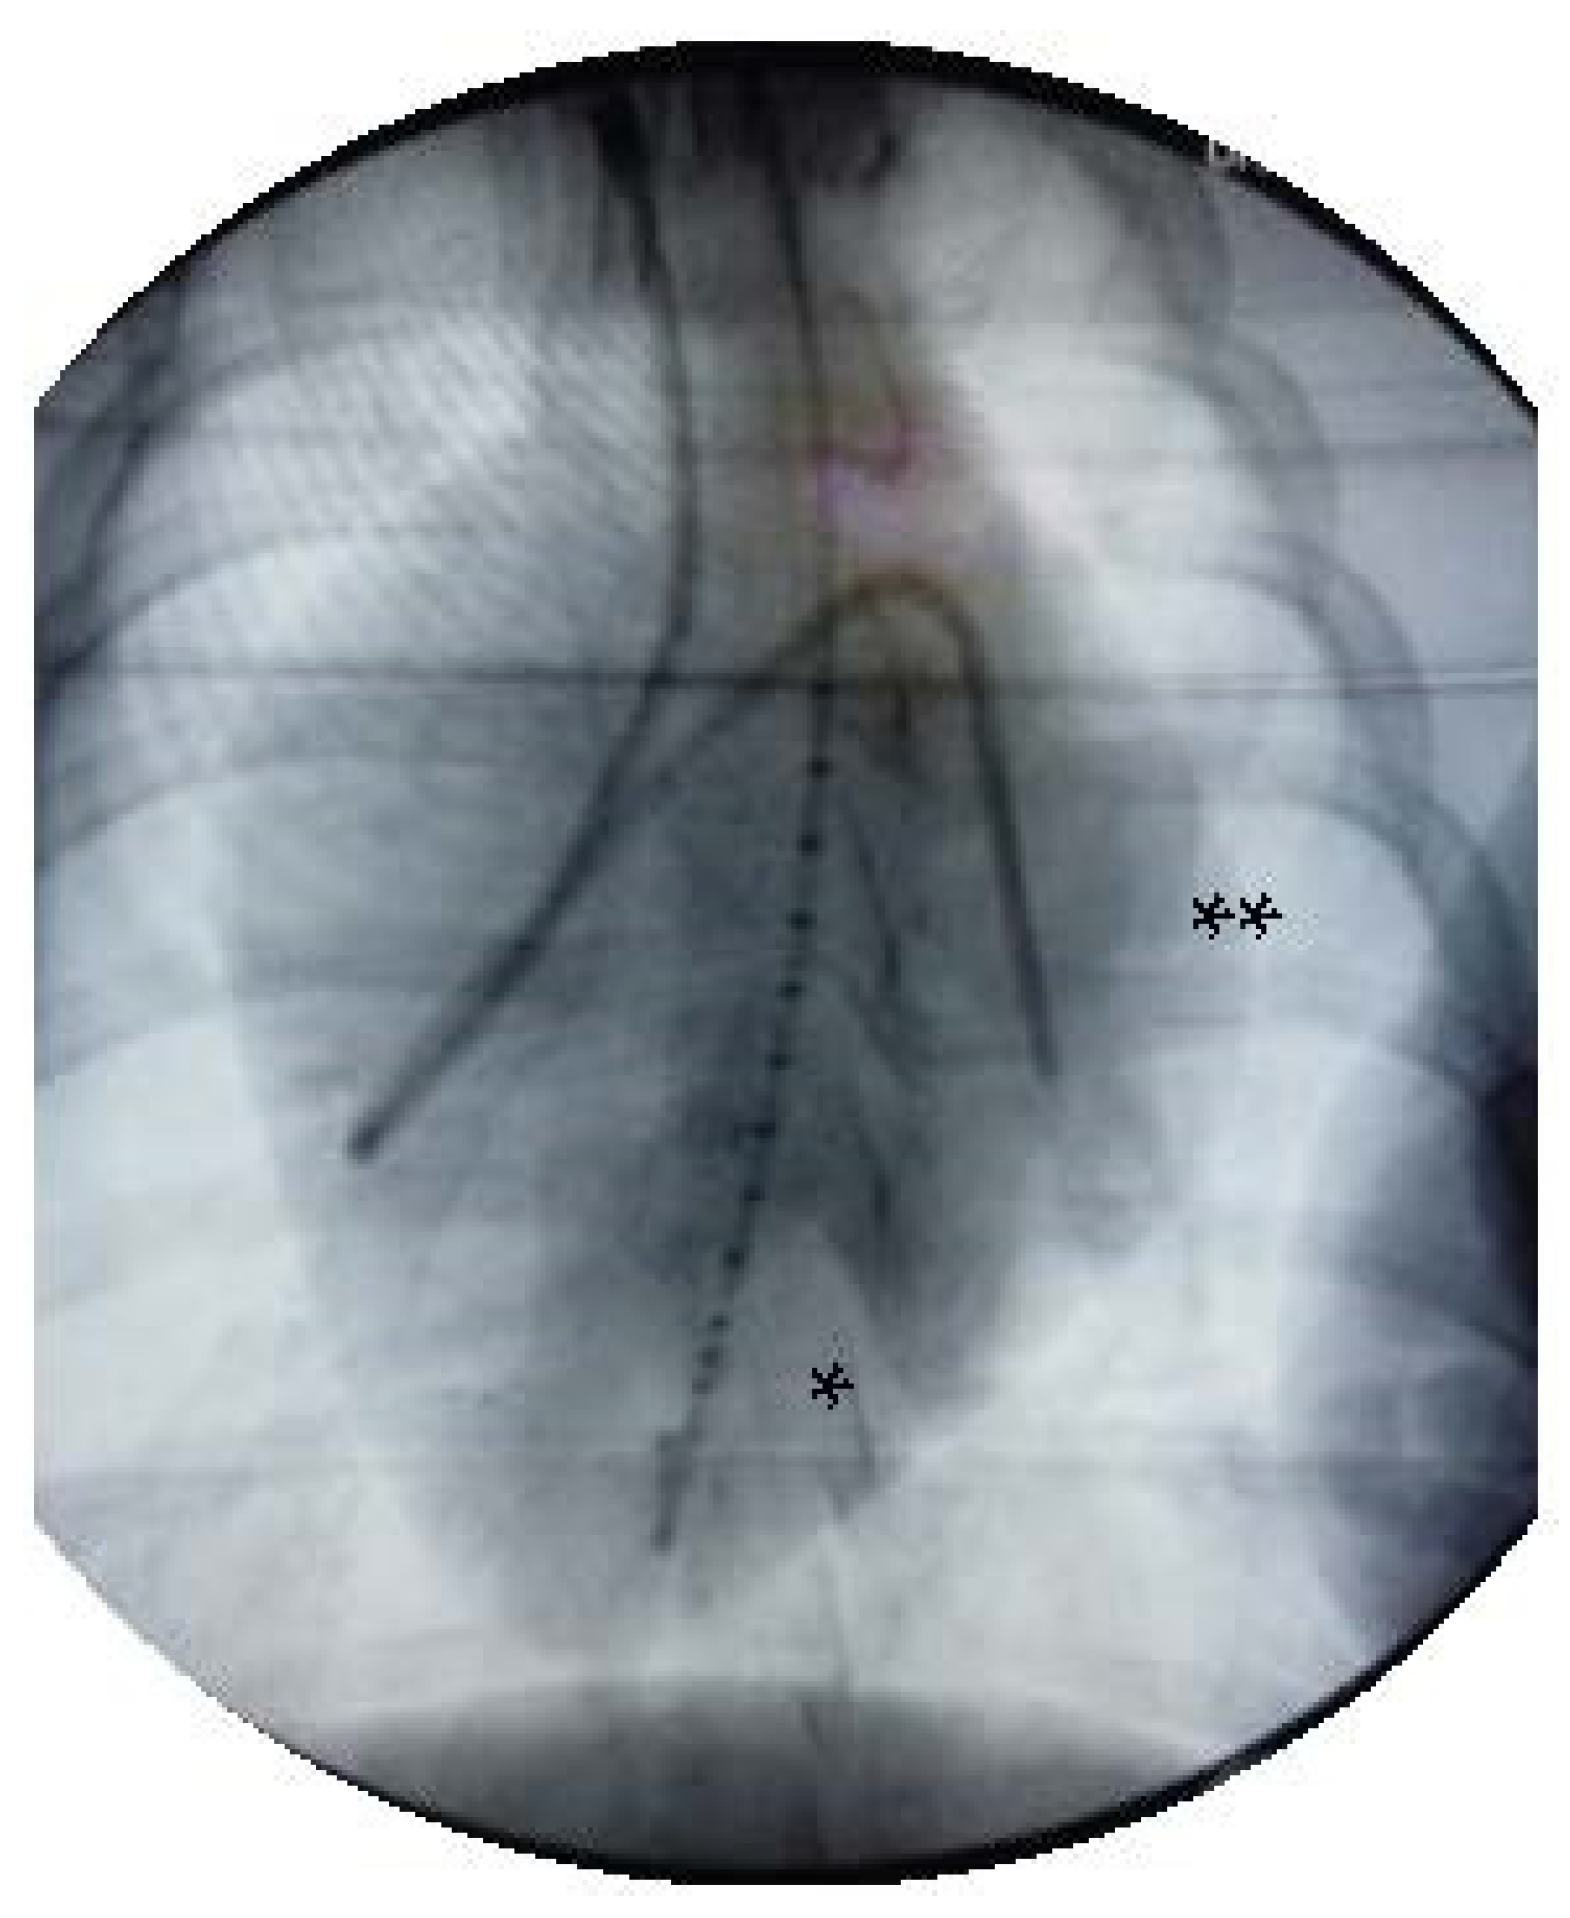

2.1. Experimental Setup